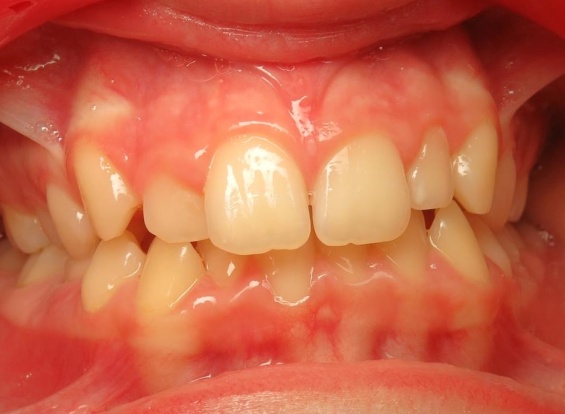

1 - Avant et après traitement

Un traitement orthopédique a permis d’optimiser la croissance des bases osseuses, offrant des conditions favorables à l’évolution de la dentition. Le traitement multiattaches a ensuite aligné les dents sur des structures squelettiques correctement développées.